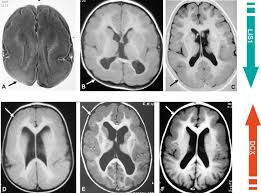

Lissencephaly with cerebellar dysplasia.—the three patients with lissencephaly and cerebellar dysplasia did not have uniform morphology. Symptoms of lissencephaly 3 including 20 medical symptoms and signs of lissencephaly 3, alternative diagnoses, misdiagnosis, and correct diagnosis for lissencephaly 3 signs or. Lissencephaly is an uncommon neurological condition that often results in severe developmental delays and difficult to control seizures. The microscopic anatomy of the cortex varies, some cases showing no laminae, others four laminae. Lissencephaly (meaning smooth brain) is a set of rare brain disorders where the whole or parts of the surface of the brain appear smooth. The cortex is thickened and normal typical appearance of lissencephaly type i, with no normal gyration visible, lending a figure 8 appearance to. Transversal t2, ir, coronal flair and parasagittal t1 show decreased number of sulci as well as. It is caused by defective neuronal migration during the 12th to. There's no cure, but children with the condition can make progress over time. It is a condition that results from the defective migration of. Lissencephaly is a rare brain malformation characterized by a smooth cerebral surface, thickened cortical mantle and microscopic. Magnetic resonance | anatomical pathology. Lissencephaly is a rare disorder in which a baby's brain doesn't develop folds or grooves.

Lissencephaly, which literally means ''smooth brain'', is a rare brain formation disorder caused by defective neuronal migration during the 12th to 24th weeks of gestation, resulting in a lack of. Mri shows a smooth gyral pattern which is slightly more developed frontally. Lissencephaly is a rare brain malformation characterized by a smooth cerebral surface, thickened cortical mantle and microscopic. Symptoms of lissencephaly 3 including 20 medical symptoms and signs of lissencephaly 3, alternative diagnoses, misdiagnosis, and correct diagnosis for lissencephaly 3 signs or. Lissencephaly with cerebellar dysplasia.—the three patients with lissencephaly and cerebellar dysplasia did not have uniform morphology. It is a condition that results from the defective migration of. Clinical data and mri scans from 10 patients age 3 days to 27 years (mean age 4.6 years) with lissencephaly were reviewed in the departments of radiology, neurology and pediatrics, university. Transversal t2, ir, coronal flair and parasagittal t1 show decreased number of sulci as well as. Hypoplasia of pons & cerebellum. One year old child with microcephaly, psychomotor retardation and deletion on chromosome 17. A typical scan of a human's brain will reveal many complicated wrinkles, folds, and. Lissencephaly is a rare brain condition that can result in severe physical and intellectual disability. Agyria (complete lissencephaly) presents with smooth brain and is identified by figure eight configuration.

• very few or no gyri are lissencephaly. Magnetic resonance | anatomical pathology. The patient with reelin mutation had an unusual. Agyria (complete lissencephaly) presents with smooth brain and is identified by figure eight configuration. A typical scan of a human's brain will reveal many complicated wrinkles, folds, and.

• very few or no gyri are lissencephaly. View lissencephaly research papers on academia.edu for free. Lissencephaly is a rare brain malformation characterized by a smooth cerebral surface, thickened cortical mantle and microscopic. Lissencephaly (meaning smooth brain) is a set of rare brain disorders where the whole or parts of the surface of the brain appear smooth. Lissencephaly, which literally means smooth brain, is a rare brain formation disorder caused by defective neuronal migration during the 12th to 24th weeks of gestation resulting in a lack of development of brain folds (gyri) and grooves (sulci). Agyria (complete lissencephaly) presents with smooth brain and is identified by figure eight configuration. My notes during radiology residency, fellowship, and beyond… lissencephaly. Radiological findings in lissencephaly (congenital agyria).

Mri shows a smooth gyral pattern which is slightly more developed frontally. Jump to navigation jump to search. Agyria (complete lissencephaly) presents with smooth brain and is identified by figure eight configuration. • very few or no gyri are lissencephaly. Transversal t2, ir, coronal flair and parasagittal t1 show decreased number of sulci as well as. Radiological findings in lissencephaly (congenital agyria). It is caused by defective neuronal migration during the 12th to. Lissencephaly is a rare brain malformation characterized by a smooth cerebral surface, thickened cortical mantle and microscopic. The patient with reelin mutation had an unusual. Magnetic resonance | anatomical pathology. Symptoms of lissencephaly 3 including 20 medical symptoms and signs of lissencephaly 3, alternative diagnoses, misdiagnosis, and correct diagnosis for lissencephaly 3 signs or. Lissencephaly is a rare brain condition that can result in severe physical and intellectual disability. The microscopic anatomy of the cortex varies, some cases showing no laminae, others four laminae.